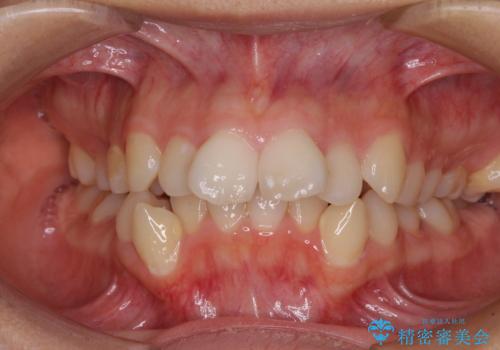

- 咬み合わせと、前歯のデコボコや八重歯、飛び出した口元を気にして来院された患者様です。

上顎は歯列不正が強く、右側臼歯部の咬み合わせは歯1本分ずれている状態でした。